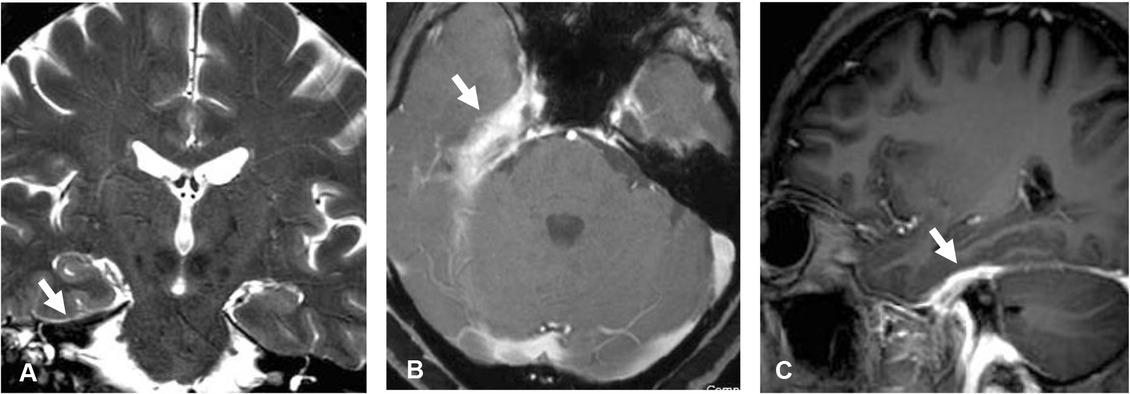

Figure 1